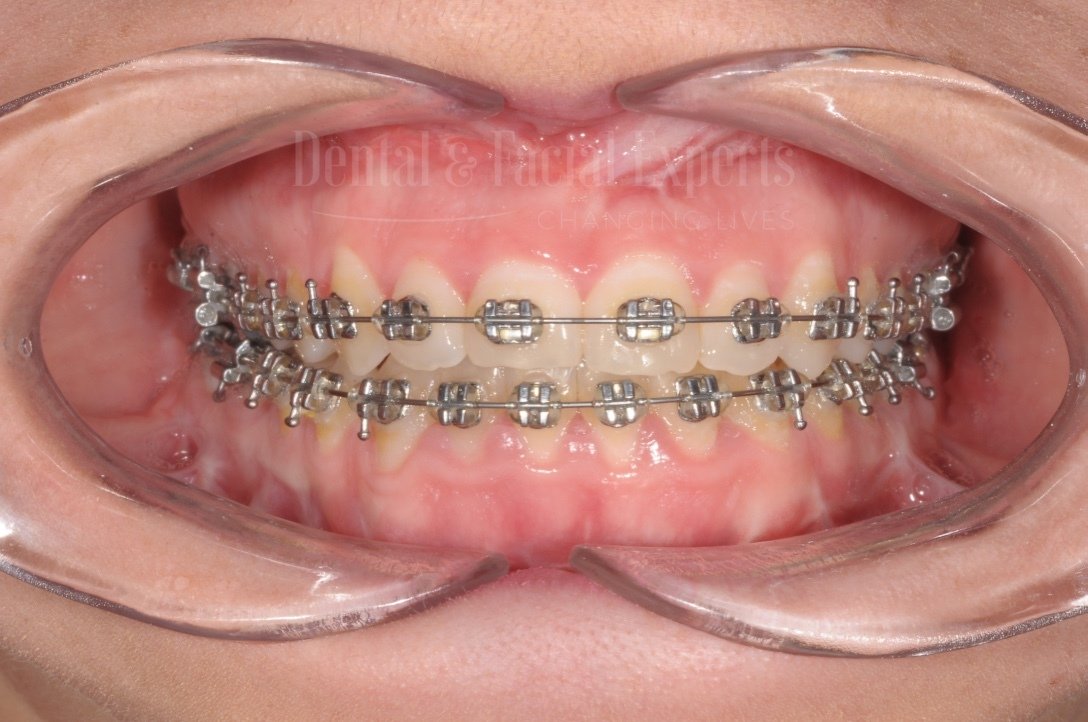

La cirugía maxilofacial es una especialidad médico-quirúrgica que aborda patologías, malformaciones y traumatismos de la cara, mandíbula, maxilares, boca y cuello. Su objetivo es restaurar la funcionalidad y mejorar la estética facial, abarcando procedimientos tanto reconstructivos como cosméticos.